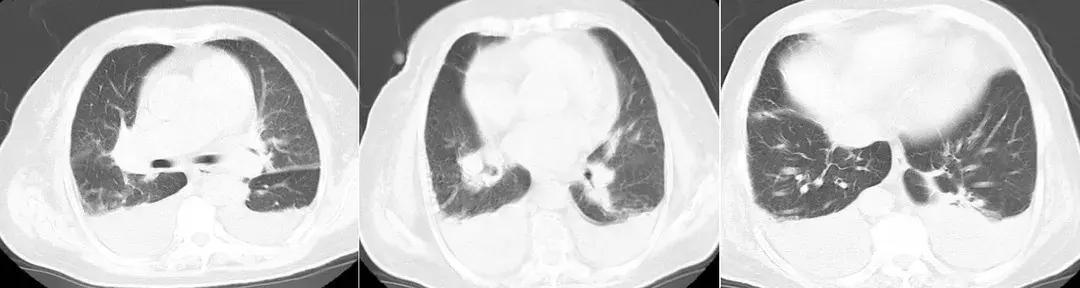

患者治疗陷入僵局,为明确呼吸困难原因,于入科第14天,行床旁心肺功能试验,同时复查肺部CT。结果提示运动心功能明显异常(见图2);肺CT(见图3)见右肺上叶、中叶改变较前无明显变化,炎症吸收好转,双侧胸腔积液。复查心脏彩超仍提示舒张功能减低,射血分数正常。

【图3】复查胸部CT:右肺上叶、中叶支气管改变,炎症吸收好转,双侧胸腔积液。